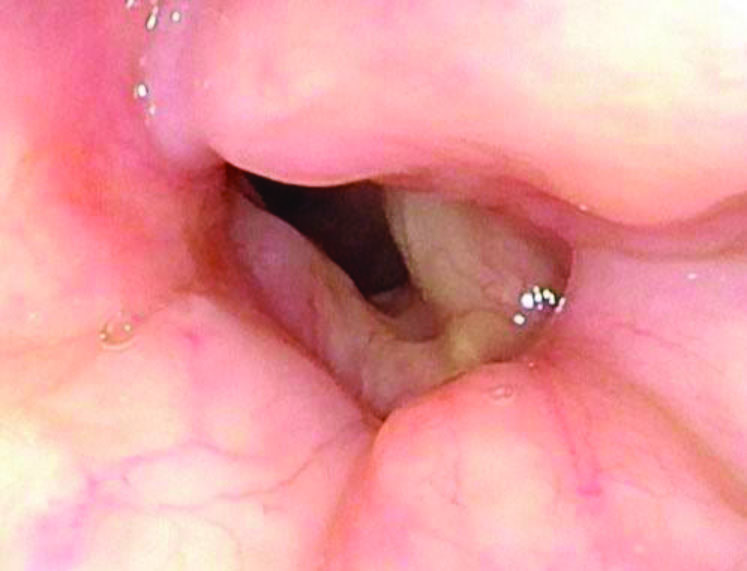

Figure 2. Preoperative office laryngoscopy showing severe posterior glottic stenosis